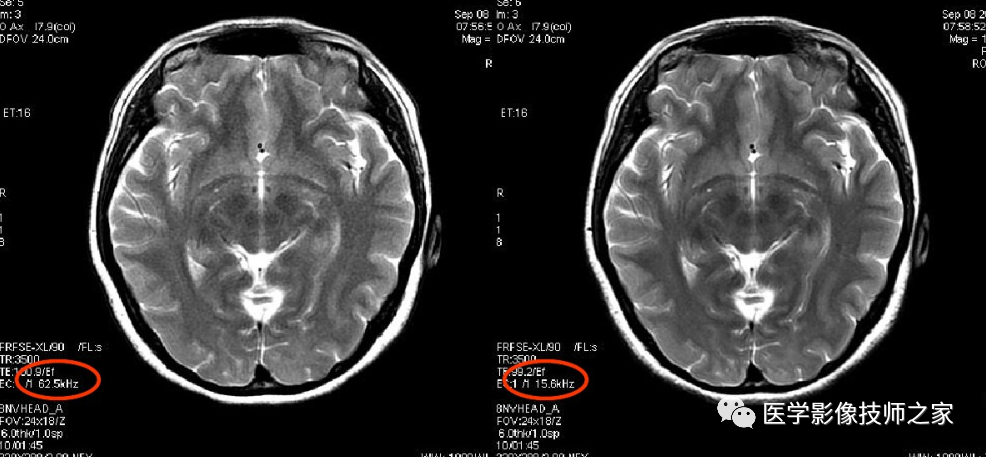

接收带宽是指 MR 系统采集 MR 信号时所接收的信号频率范围。减少接收带宽可以提高图像的信噪比,但可导致图像对比度下降。同时,减少扫描层数,扫描时间延长,并增加化学位移伪影。MR 激发脉冲使用的是射频波,其频率范围称为射频带宽或发射带宽。射频脉冲的持续时间越短,即脉冲的形状越窄,傅里叶变换后其频带带宽越宽。层面厚度与带宽成正比,即层厚越厚,带宽越宽。人体组织信号为不同频率信号的叠加, 包括被激励的组织和噪声。射频带宽越宽, 信号采集范围就越大, 噪声也越大。

1、SNR与RBW的平方根成反比,所以降低RBW可以在一定程度上提高SNR,但必须注意:过低的RBW会使MinTE或ESP增加,故在T1加权像过低RBW可导致T1对比度变差,而在T2加权像则可能导致模糊伪影加重

2、1.5TRBW一般设定大于31kHz